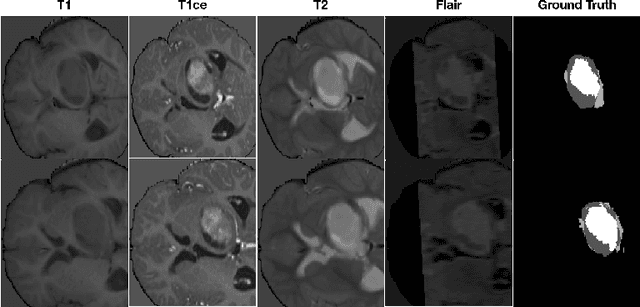

Abstract:Data augmentation is an effective and universal technique for improving generalization performance of deep neural networks. It could enrich diversity of training samples that is essential in medical image segmentation tasks because 1) the scale of medical image dataset is typically smaller, which may increase the risk of overfitting; 2) the shape and modality of different objects such as organs or tumors are unique, thus requiring customized data augmentation policy. However, most data augmentation implementations are hand-crafted and suboptimal in medical image processing. To fully exploit the potential of data augmentation, we propose an efficient algorithm to automatically search for the optimal augmentation strategies. We formulate the coupled optimization w.r.t. network weights and augmentation parameters into a differentiable form by means of stochastic relaxation. This formulation allows us to apply alternative gradient-based methods to solve it, i.e. stochastic natural gradient method with adaptive step-size. To the best of our knowledge, it is the first time that differentiable automatic data augmentation is employed in medical image segmentation tasks. Our numerical experiments demonstrate that the proposed approach significantly outperforms existing build-in data augmentation of state-of-the-art models.